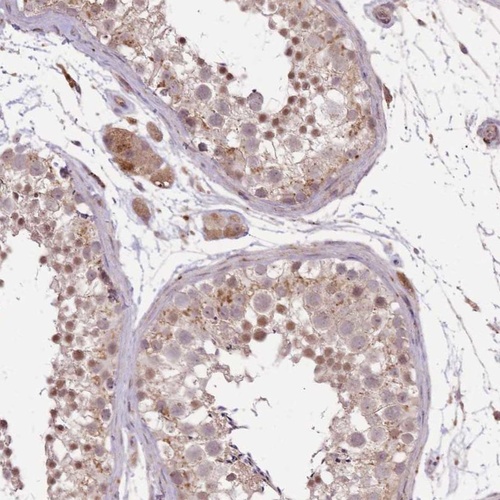

Immunohistochemical staining of human testis shows cytoplasmic and nuclear positivity in cells in seminiferous ducts.